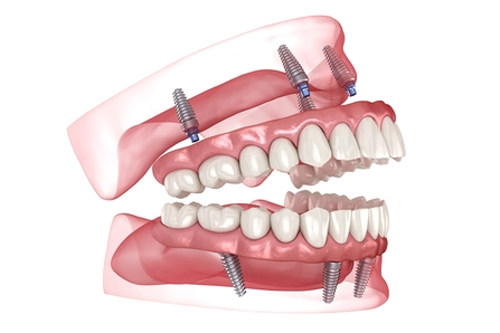

种植牙不是“一颗一颗种”,而是像搭积木一样需要整体设计。32颗牙的种植方案直接影响总价:

全口半固定种植:上下颌各植入2-4颗种植体,通过球帽或杆卡连接活动假牙,总价约6-8万元。适合牙槽骨萎缩重度的老年人,但咀嚼力有限,啃苹果需谨慎。

All-on-4/6即刻负重:上下颌各植入4或6颗种植体,当天装临时牙冠,总价约12-15万元。一位北京患者在私立医院选择All-on-6,用韩国奥齿泰植体+国产全瓷冠,总价13.8万元,术后3天啃排骨无压力。

传统全口种植:32颗牙逐颗植入,总价可达18万元以上。适合年轻患者或对咀嚼力要求极高的人群,但手术创伤大、改善期长,需谨慎选择。